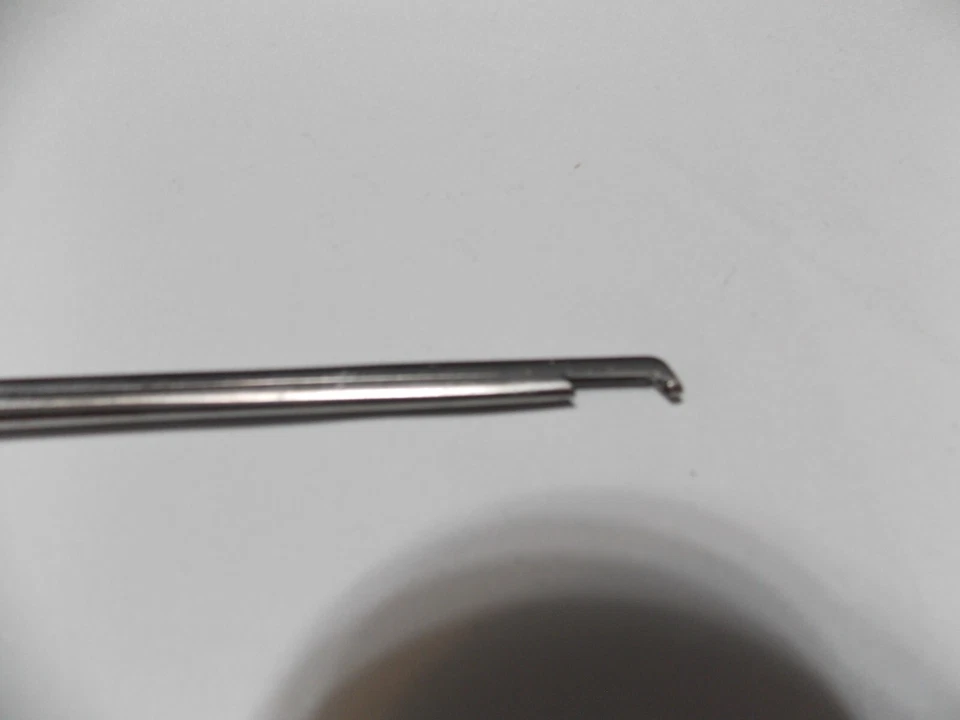

ORANGE OR 4-88 WECK 40 Deg 2mm UP Bite 8″ Shaft Neuro Spine (LAM-1653)

ORANGE OR 4-88 WECK 40 Deg 2mm UP Bite 8″ Shaft Neuro Spine

(LAM-1653)

THIS LOT IS SOLD AS SHOWN IN THE PICTURES